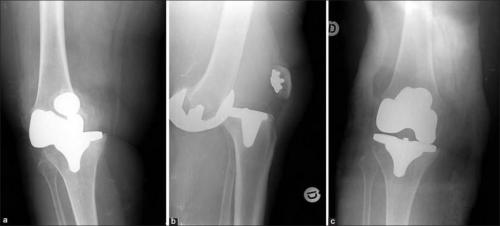

Такое может случиться, если очень торопиться. Это вывих коленного импланта.

Реабилитация после эндопротезирования имеет первостепенное значение для обеспечения безболезненного функционирования сустава и улучшения качества жизни пациента. Операция попоказана для лечения болезненных и инвалидизирующих патологий, вызванных различными формами, тяжелыми травмами. Хирургом-ортопедом выполняется полная или частичная замена износившегося суставного соединения на его анатомически точную копию.

Искусственный имплантат состоит из металлических и пластиковых элементов, абсолютно безопасных для организма. Чтобы заново научить прооперированную конечность двигаться правильно, расширить диапазон доступных движений, требуются массажи, посещение физиотерапевтического кабинета, выполнение.